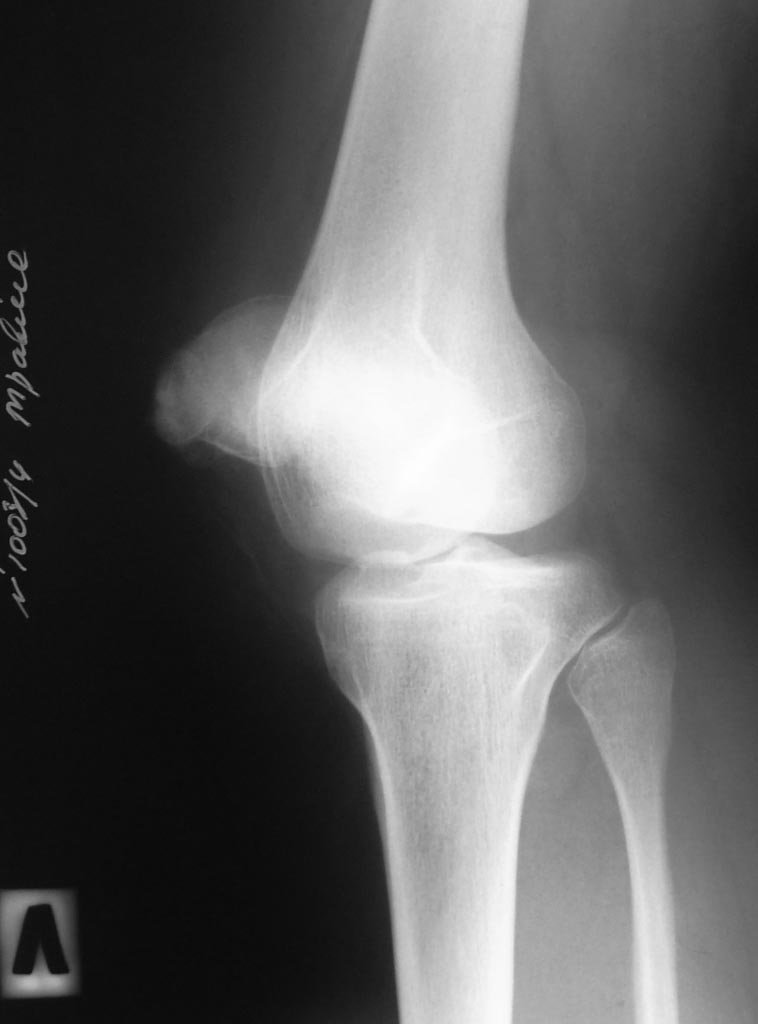

В травматологическом отелеении находится 16 летний юноша с пателло-феморальным артрозом, вторичной деформацией мыщелка бедра и надколенника. Глубокоуважаемые коллеги!Просим вас прокомментировать тактику лечения представляемого больного.Крупный ребёнок 16 лет. Избыточный вес. Не заинтересован в физических нагрузках. Обратился с жалобами на боли в левом коленном суставе при ходьбе. В 2011 году находился на стационарном лечении в нашей кинике по поводу застарелого перелома внутреннего края левого надколенника с разрывом капсулы сустава, хондромаляции наружного мыщелка бедра и гемартроза. За год до госпитализации перенёс двукратный спонтанный вывих левого надколенника. В отделении (март 2011 года) выполнена артроскопия, санация гиалинового хряща наружного мыщелка. Артропластика по Кемпбеллу. Рентгенограммы той поры не сохранились. Через 2 месяца после оперативного лечения ребёнок находился в отделении по поводу послеоперационной-посттравматической разгибательной контрактуры коленного сустава. После выписки больной исчез из поля зрения. Повторно обратился только в настоящее время. При осмотре: Походка не изменена. Вальгусная деформация коленных суставов: справа – 12, слева 15. Движения в коленных суставах в полном объёме. Выпот не определяется. Наружная ротация левой стопы 15-20 градусов. Левый надколенник латеролизован. При сгибании левого коленного сустава происходит наружная дислокация надколенника. Фото больного и результаты рентгенологического обследования прилагаем (будут выкладываться последовательно). Исходя из жалоб и результатов обследования, нами рассматривается следующий вариант хирургической помощи больному. Надмыщелковая остеотомия бедра, выполнение 15 градусов внутренней ротации дистального сегмента, его варизирующее отклонение на 15 град. до исправления вальгуса (анатомической оси конечности ). Очень сомневаемся в отношении вмешательства на поддерживающем аппарате надколенника. Мнения разделились: сделать латеральный релиз , либо не трогать совсем. Делать ли дупликатуру медиального отдела капсулы? Вызывает опасения неконгруентность суставной поверхности надколенника. Рассматриваем вариант V-образной остеотомии надколенника. Следует ли «подгонять» такой надколенник по мыщелку или оставить в надежде на постепенную перестройку. Как одна из ожидаемых проблем после выполнения вмешательства – резкое ограничение сгибания, так как в настоящее время надколенник «уезжает» с мыщелка при сгибании – что, скорее всего, вызвало укорочение квадрицепса и собственной связки надколенника. Может ли появиться необходимость вмешательства на собственной связке и бугристости одномоментно?Больной не настаивает на оперативном лечении. Родители же согласны с необходимостью коррекции. Как один из вариантов – не трогать нам его совсем. Живёт же . Будем благодарны за соображения, подсказки и опыт похожих ситуаций.

А вариант с переносом бугристости б/б кости не рассматриваете? Контралатеральная конечность тоже в вальгусе, но там же надколенник не латерализуется. Вальгус, наверное, не основной момент нестабильности. На аксиальном снимке - явная дисплазия наружного мыщелка. Не исключен ещё и вариант patella alta - на фотографиях не очень понятно. Наверное, всё же без укрепления медиального отдела и релиза латерального будет не обойтись.

Рассматриваем такой вариант. Но тогда - придётся делать кондилолеваторопластику наружного мыщелка бедра. А этого не хотелось бы по причине смутных перспектив такого подхода. Если Вы посмотрите на взаимоотношение мыщелков ("понижение" наружного" - то, скорее всего, надколенник просто так не удержится. Исправление вальгуса, по нашему скромному мнению, приведёт к бОльшей медиализации надколенника (за счёт смещения векторов тяги квадрицепса). Как будет чувствовать себя надколенник с "обратной" формой и неоартрозом на новом месте? Всё-таки?

Обязательно латеральный релиз, транспозиция бугристости медиально, пластика медиального ретинекулюма. Надколенник скорее всего годам к 20 будет "лысым" если ничего не делать. Возможно, что уже хондромаляция 3 ст. Вместо остеотомии бедра лучше сформировать латеральный мыщелок "приподняв" его. И все будет о.к. А вальгус потом, если захочет, остеотомией б/б кости. И неплохо бы резекцию желудка :)

На фото этого крупного подростка и снимках видно, что проблема не в отдельно взятом артрозе пателло-феморального сочленения. Отчетливо вида вальгусная установка колена, продольное плоскостопие, значительная торзия бедра кнаружи, очевидна дисплазия латерального надмыщелка бедра. Коррекция одномоментная всего этого вряд ли возможна, да и не рвутся на нее родители.Возможно сейчас можно обойтись малой кровью- эндоскопическим латеральным релизом надколенника, полечить имеющийся ОА гиалуроновой кислотой, заставить носить стельки и сбросить вес.После завершения роста, при наличии клиники ОА, а она непременно будет, возможны и варизующая высокая тибиальная остеотомия и возможна транспозия бугристости. Но вариант удаления надколенника или его остеотомии я бы всерьез не рассматривал- последствия непредсказуемы.